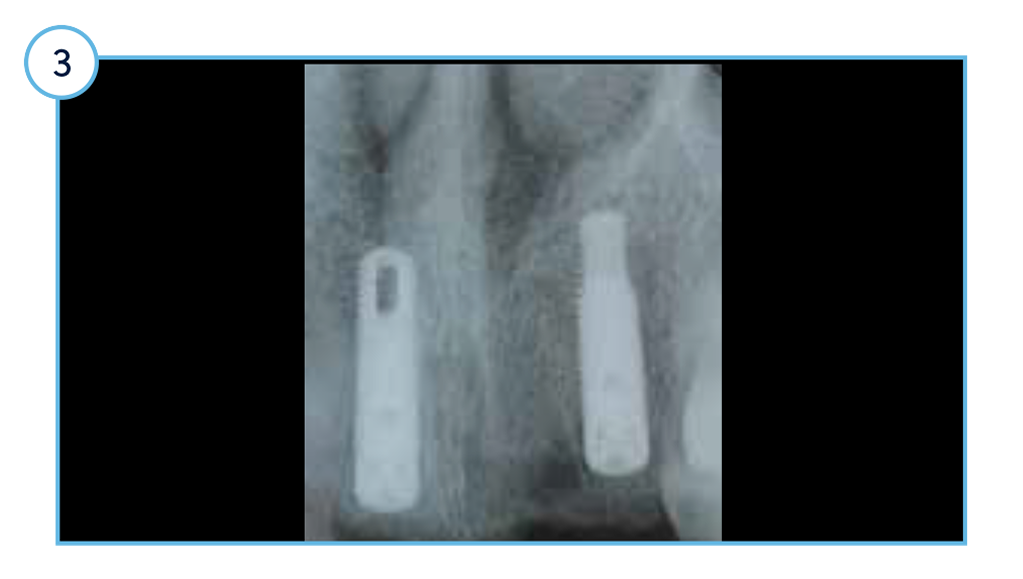

One-year post-placement radiograph with stable marginal bone levels around TSVT implants.